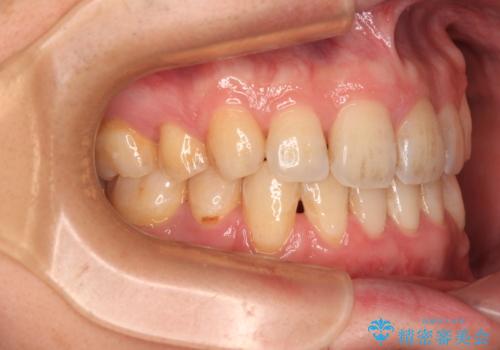

出っ歯と八重歯 目立たない裏側装置でスッキリとした口元に

- 上顎の前突感による口の閉じにくさと八重歯を気にして来院された患者様です。

下顎骨が左側に大きく変位しているため、上下の正中位置は極力一致するところをゴールとしました。

上下顎で左右差の大きい抜歯矯正を裏側装置で行ったため、非常に時間がかかりましたが、正中位置も良い位置に改善され、気になっていた突出感も解消されました。